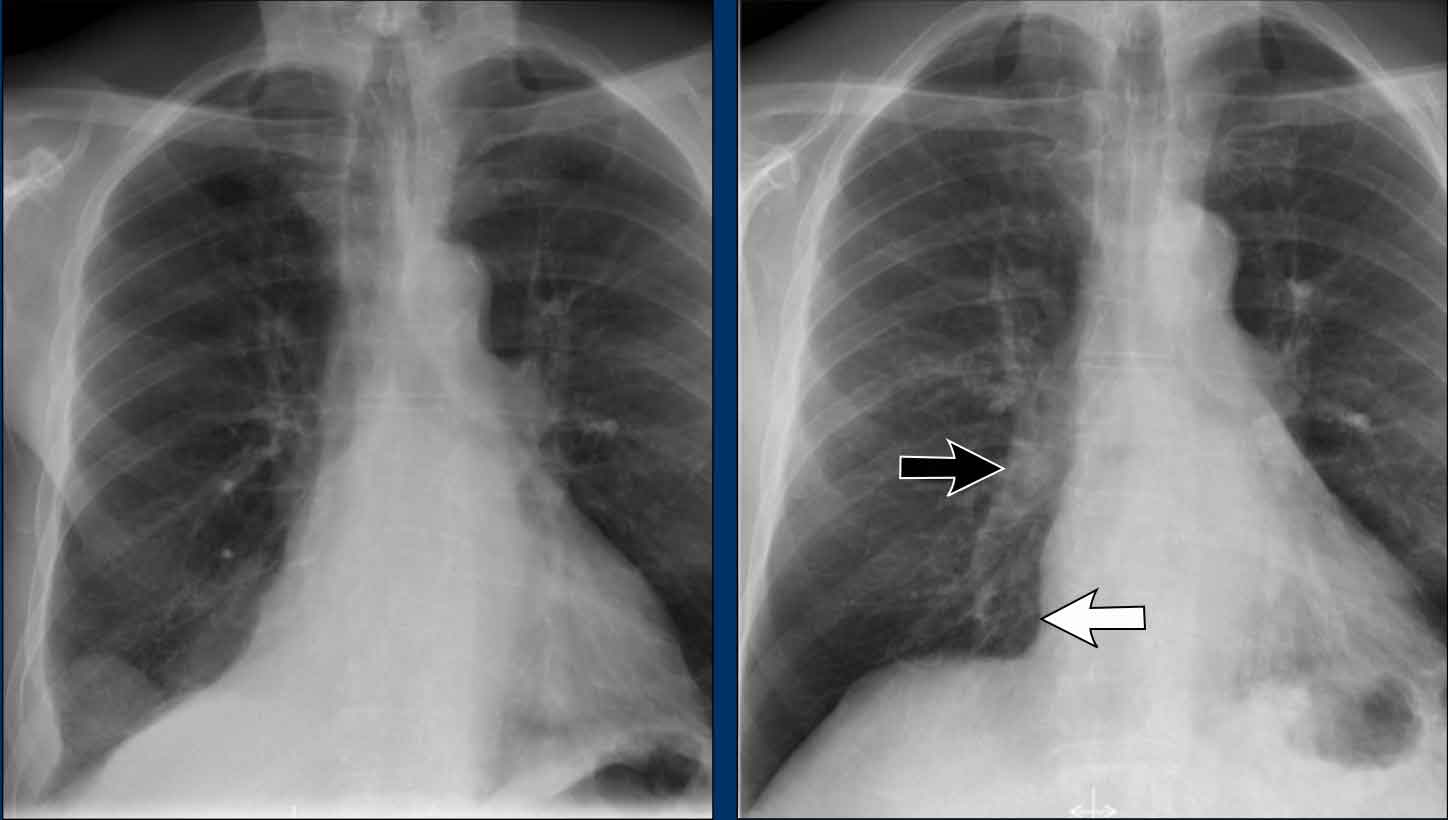

Hidden Areas (4): Retrocardiac Opacity

Initial review of the CXR reveals a subtle increase in density in the retrocardiac region (blue area), which requires careful attention.

• This was confirmed to be a left lower lobe pneumonia.

• Always correlate with the lateral view, where consolidation in the lower thoracic spine region is a key clue.